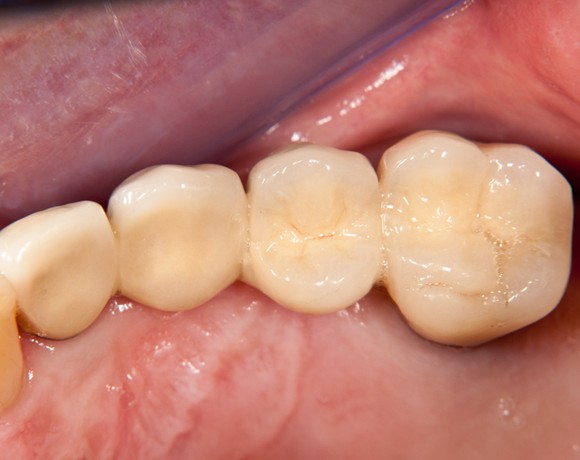

Bei dieser Patientin mussten die Zähne 22,26 und 27 aus parodontalen Gründen entfernt werden. Nach Extraktion der Zähne 22 und 26 wurden sofort in die Extraktionsalveolen die Implantate gesetzt. Zahn 27 war bereits sechs Monate zuvor extrahiert worden und die Knochenwunde gut ausgeheilt. Das geringe Knochenangebot wurde mit einem internen Sinuslift ausgeglichen. Im Bereich des Zahnes 23 wurde noch ein weiteres Implantat gesetzt. Da der Zahn 12 nicht angelegt und die Symetrie auf dieser Seite gestört war, wurden die Zähne 11 und 13 mit Teilkronen versorgt, um die Lücken zu schließen der Zahn 13 zu 12 umgebaut.